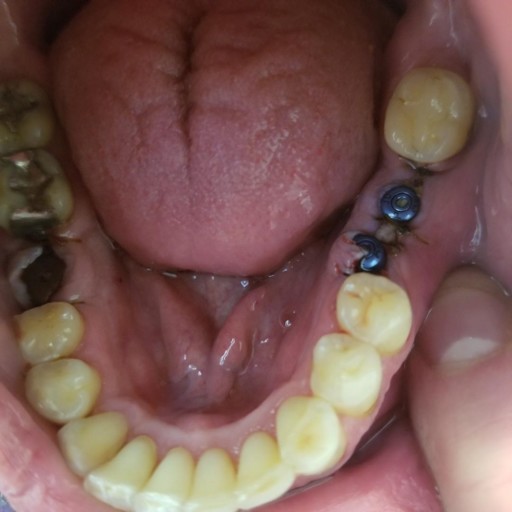

I had an implant put in about 3 years ago. I am a non smoker but in the last 6-12 months, have developed a "clenching problem". I do wear a bite guard at night but prior to this issue, I probably only wore it about 70% of the time. In the last 7-10 days, I have noticed an "awareness" of my implant. It doesn't hurt. More that it feels as if I've had recent dental work and have that very dull pressure feeling. I had a regular dental cleaning and exam including regular xrays as well as the super duty xray that orbits the head. Nothing was noticed then but that was prior to me having these feelings. I started a new job about 5 months ago and just found out that no procedures related to my implant are covered so I am VERY concerned. I should also note that when I look at myself in the mirror while clenching, I do not see this particular tooth being touched in any way by the other teeth. I don't think I am guilty of clenching during the day but I do catch myself kind of "locking" my jaw. So perhaps this is more related to jaw fatigue? Hoping you can give me some hope that this will not lead to implant failure and what steps I could take to improve things. I did make an appt with my dentist for 10/03. He is not the dentist that put in the implant though.

I had 3 implants done yesterday, with 2 that were next to each other (see picture). One is not aligned. I am also doing ortho care and went in today to have a new retainer fitted. The dentist said he did not want to do new impressions due to the...